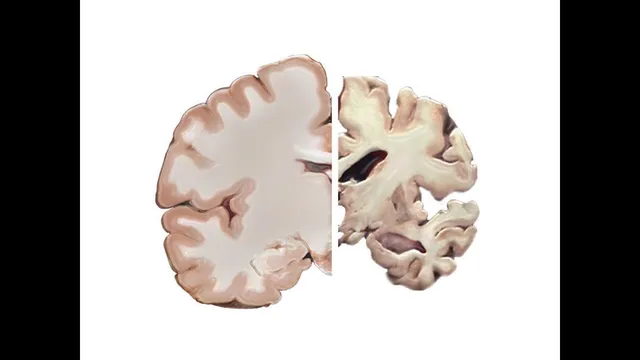

Alzheimer’s disease is driven by physical damage inside the brain—especially the buildup of sticky protein structures—yet it also remains stubbornly hard to predict or stop. The condition affects memory and thinking, and it becomes more common with age, but it isn’t considered a normal part of aging. From 2000 to 2013, Alzheimer’s rose as a cause of death even as many other causes declined, underscoring why researchers keep searching for ways to prevent it, delay it, or slow its progression.

Alzheimer’s is linked to two major microscopic abnormalities: plaques and tangles. Plaques form when fragments of a protein called amyloid precursor protein (APP) are processed in ways that produce amyloid-beta. Enzymes such as alpha-secretase and beta-secretase cut APP into different fragments, and gamma-secretase can further process them. When amyloid-beta isn’t cleared efficiently—or when it folds incorrectly—small clumps called oligomers can form. Those oligomers can then grow into larger structures known as plaques. Plaques are associated with brain cell damage, and oligomers are suspected to be especially toxic, potentially allowing unregulated ion flow into neurons.

Tangles involve another protein, tau (often referred to as “TOA” in the transcript), which normally stabilizes microtubules—cellular “railroad ties” that help guide nutrients and other materials. In Alzheimer’s, tau becomes abnormally sticky and tangles with other tau proteins, disrupting the delivery network inside neurons.